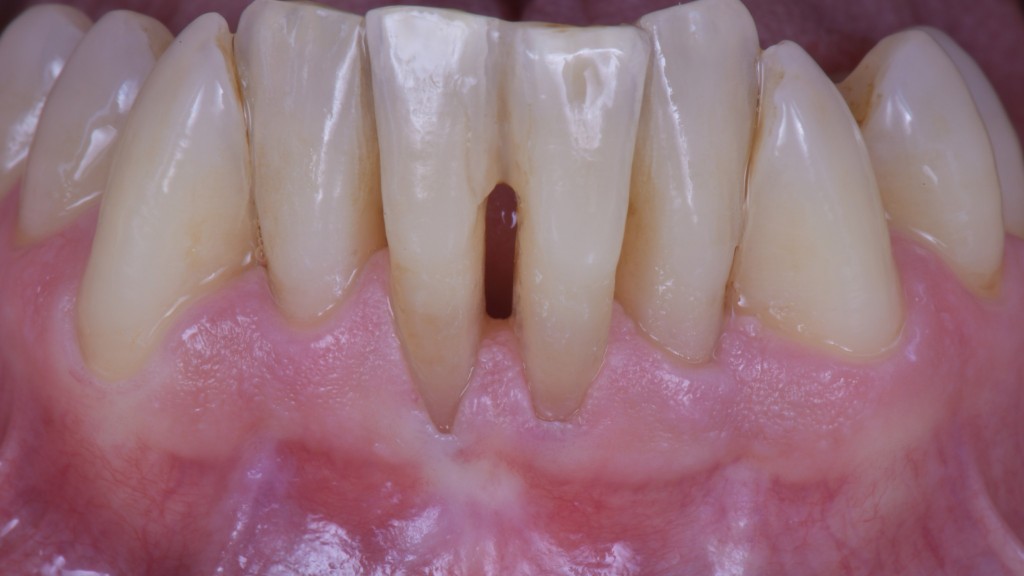

Il mio paziente si era presentato in visita con una ferita ricorrente da spazzolamento facilitata dalla scarsa qualità dei tessuti e dalla completa assenza di tessuto cheratinizzato.

In un caso del genere, vista la grave perdita di attacco, una ricopertura radicolare completa sarebbe ovviamente impossibile ed una ricopertura parziale sarebbe difficilmente predicibile nel risultato. Dopo la terapia causale e le istruzioni d’igiene con conseguente risoluzione della lesione, ho allora deciso di limitarmi a creare una banda di tessuto cheratinizzato che consentisse al paziente di spazzolare sereno…